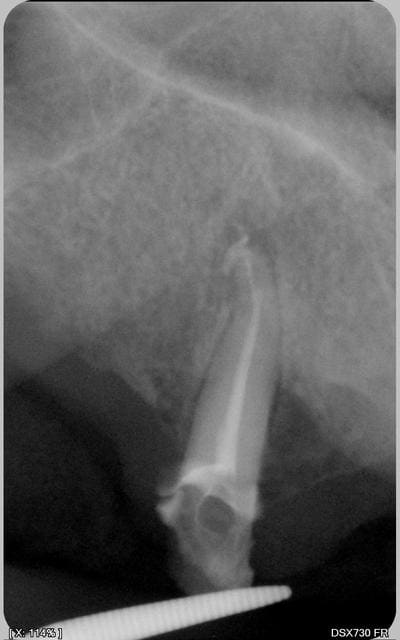

Je fais donc partie des abrutis qui tiennent de temps en temps le capteur (réflexe nauséeux, petites bouches , enfants, patients pas doués ou dégoûtes de se mettre les doigts dans la bouche,....) dans les cas ou j'arrive pas a mettre l'angulateur.

Bon, ça c’était jusqu'a ce matin ou avec mon croissant j'ai pu admirer la super photo et je me suis dit que plus jamais.

Donc, merci cyber, ce post sert a quelque chose, et pour don chicot, j'avais les memes chiffres. Mais bon, comme je caresse encore l’idée d'apprendre le piano...

Ici, le praticien a certainement été obligé d'enlever le crampon pour faire son cliché post-endo, il aurait donc pu placer un angulateur.

Et s'il n'y avait pas de dents antagonistes pour serrer sur l'angulateur, reste la possibilité de le faire tenir par le patient.